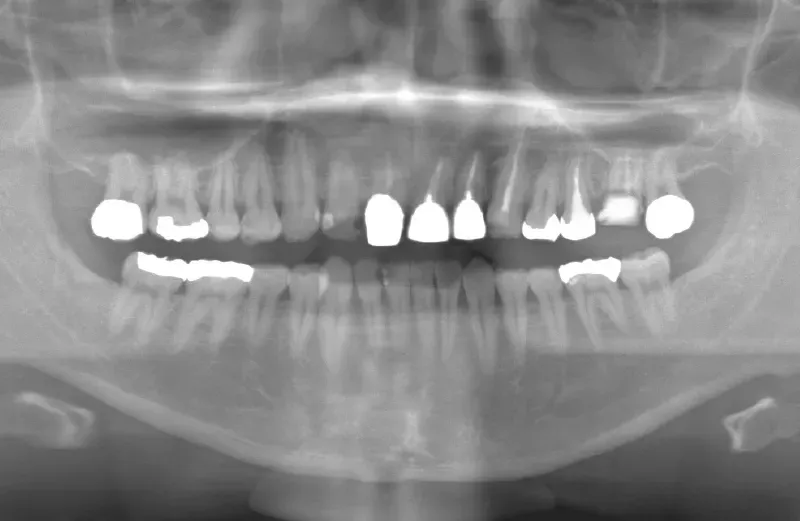

メガジェンオペの症例紹介01

治療前

治療後

| 主訴 | 上入れ歯は以前に入れたことがあるが違和感が強く入れられなかったのでインプラントで治療して欲しい。 他院では上顎洞までの垂直骨量が1~3mm程度しかないのでサイナスリフトが必須であり、インプラント治療で歯が入るまでに1年以上かかると言われたのでセカンドオピニオンを希望で来院。 |

| 治療期間 | 2.5ヶ月で仮歯が入り、 4ヶ月で最終補綴物が入って終了。 |

| 費用 | 約1,500,000円 |

| 治療内容 | エクストラワイドショートインプラントを埋入し、上顎洞を移植材を用いずに挙上しインプラントを埋入した。約2.5ヶ月で仮歯を装着し、様々な機能面に問題がないことを確認し4ヶ月で最終補綴物を装着して終了した。 |

| 治療のリスク | インプラント埋入オペ時に術者が上顎洞内にインプラントを迷入させる可能性がある。これは術者が技術的に熟練していれば防ぐことが可能。 |